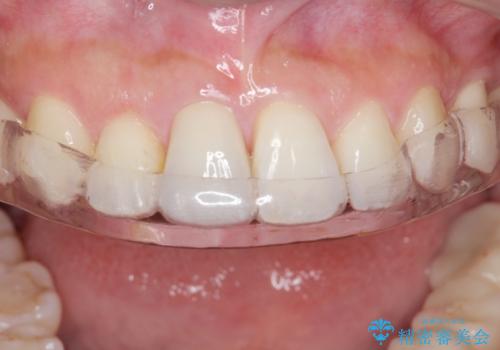

今後、詰め物や被せ物が歯軋りなどで割れないように、また歯のすり減りの防止のためナイトガードを作製しました。

- 自費ナイトガード 3.3万円費用は治療当時の料金となります

ナイトガードは夜寝ている時に使用するものですがその時、矯正の後戻り防止の装置としても機能します。